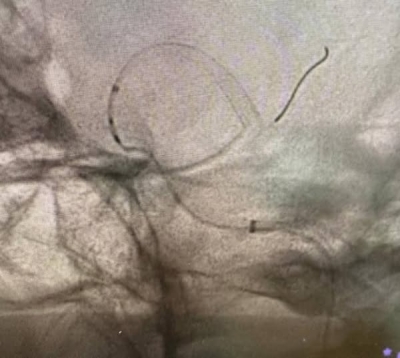

وخلال العملية، تم تركيب شبكة دقيقة بين الشريان الدماغي الأوسط والشريان السباتي الداخلي، ما ساعد على تحويل مسار الدم بعيدًا عن الكيس الدموي المنفجر، وبالتالي وقف النزيف بشكل كامل .

وأوضح الأستاذ الدكتور موفق الحيص أن هذه العملية تُعد من العمليات المعقدة والدقيقة جدًا، وتتطلب مهارة عالية في التعامل مع الأوعية الدموية الدماغية، مشيرًا إلى أن المستشفى يمتلك كوادر طبية مؤهلة وأجهزة متطورة تمكّنه من إجراء مثل هذه التدخلات العصبية الدقيقة .